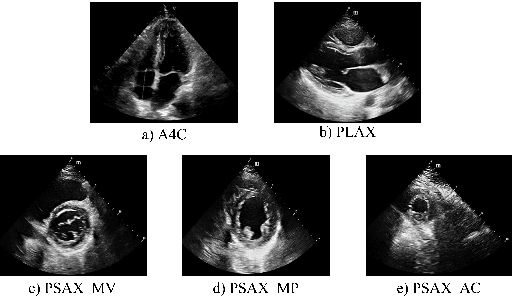

Abstract:Hypertrophic cardiomyopathy (HCM) and cardiac amyloidosis (CA) are both heart conditions that can progress to heart failure if untreated. They exhibit similar echocardiographic characteristics, often leading to diagnostic challenges. This paper introduces a novel multi-view deep learning approach that utilizes 2D echocardiography for differentiating between HCM and CA. The method begins by classifying 2D echocardiography data into five distinct echocardiographic views: apical 4-chamber, parasternal long axis of left ventricle, parasternal short axis at levels of the mitral valve, papillary muscle, and apex. It then extracts features of each view separately and combines five features for disease classification. A total of 212 patients diagnosed with HCM, and 30 patients diagnosed with CA, along with 200 individuals with normal cardiac function(Normal), were enrolled in this study from 2018 to 2022. This approach achieved a precision, recall of 0.905, and micro-F1 score of 0.904, demonstrating its effectiveness in accurately identifying HCM and CA using a multi-view analysis.